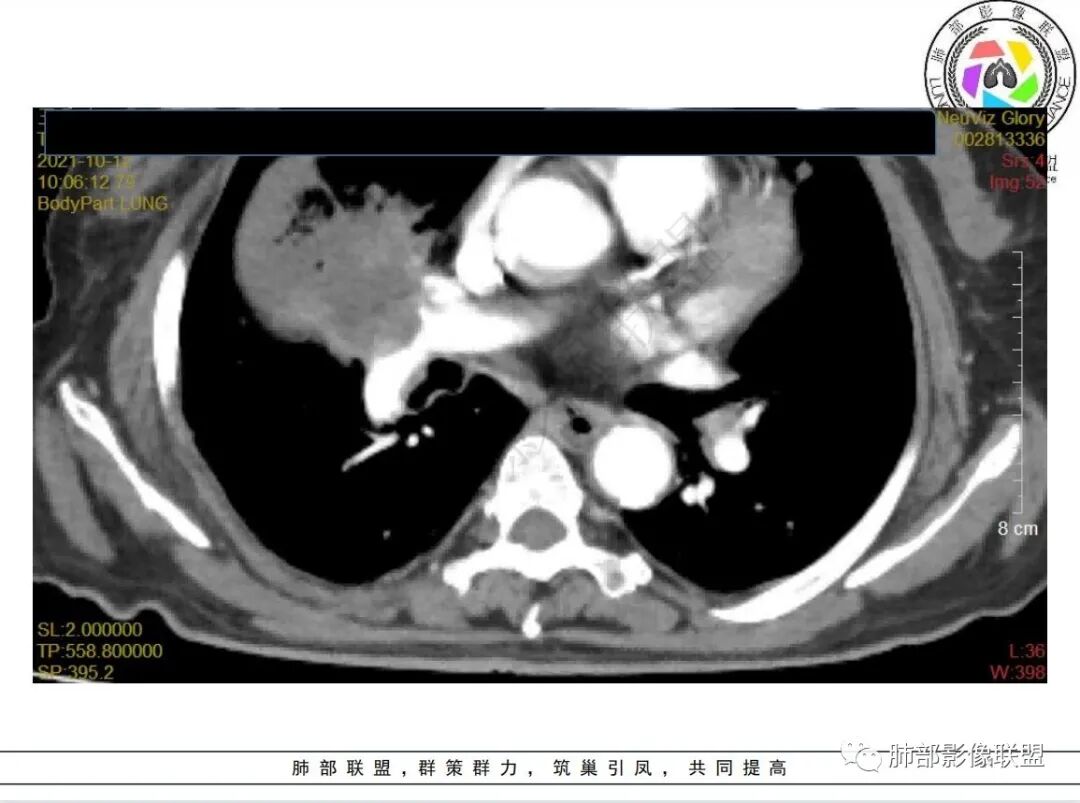

白血病化疗后,出现多发结节,边缘可见晕征,病灶内可见多发坏死,右肺中叶肺动脉可见充盈缺损,右肺中叶可见融冰征,考虑毛霉菌,右肺中叶肺动脉栓塞伴右肺中叶肺梗死。

4.白血病化疗后,CT上出现多发结节,边缘可见晕征,病灶内可见多发坏死,右肺中叶肺动脉可见充盈缺损,右肺中叶可见融冰征,右肺中叶肺动脉侵犯栓塞伴右肺中叶肺梗死,可符合真菌感染。

血管侵袭性曲霉病是最常见的类型,其特征是真菌菌丝侵入和阻塞中小肺动脉,形成凝固性坏死、肺泡出血或出血性梗死。

6.肺曲霉病典型的CT表现是结节周围有磨玻璃样的晕征表现,或胸膜为宽基底的楔形实变。晕征表现为曲菌感染的肺结节伴梗死和凝固性坏死,周围有肺泡出血。最终可出现空泡征象,并可观察到中央坏死组织与周围肺实质分离形成空气新月征。